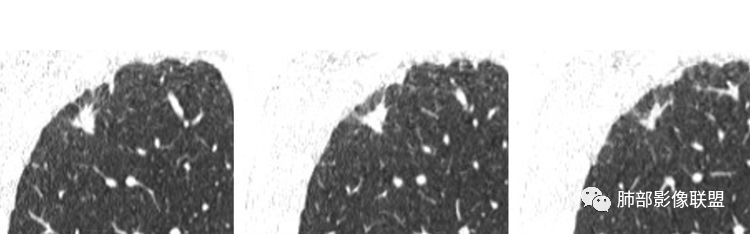

2.右肺上叶胸膜下不规则实性密度小结节影,密度均匀。边界清楚,缺乏典型深分叶,除个别层面上圆隆外,大多边缘平直甚至内凹,成三角形轮廓,冠状位甚至状如“奔驰”车标。

3.可见棘状突起或条索影牵于胸膜间,胸膜侧可见毛刺。灶周未见磨玻璃影。

4.周围肺组织见小结节影,胸膜多见结节样增厚。

5.肺门及纵隔未见增大淋巴结。